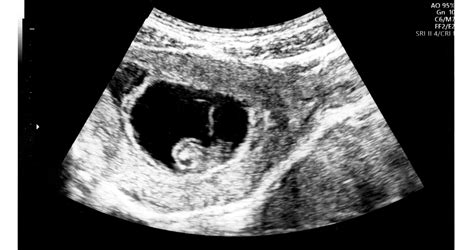

A panaszokkal jelentkező páciensnél az anyai tünetek felmérésével egy időben tisztázni kell a magzat állapotát. Az egyik legfontosabb lesz ezután a laborvizsgálatok elkészítése, amelyek segíthetnek elkülöníteni az akut zsírmájat más betegségektől. A laborokban a májelégtelenség jelei lesznek láthatóak. Amikor igazolódik a májelégtelenség, vagy a kóros májműködés, akkor kiegészítő laborvizsgálatokkal és ritkán képalkotó vizsgálattal lehet pontosítani a panaszokat kiváltó okot. A máj egyéb betegségeit is vizsgálni kell, mert lehetnek olyan, terhességtől függetlenül jelentkező kórokok, amelyek kiválthatnak májkárosodást (vírusos májgyulladás, epeút-elzáródás, mérgezések, stb.) is.

A zsírmáj diagnosztizálása: A betegvizsgálatnál az orvos fizikális vizsgálatot végez, melynek során észlelheti a fent részletezett tüneteket, illetve tapinthatja a kemény, megnagyobbodott májat. Laborvizsgálatok is jelzik a betegségre jellemző kóros értékeket. A képalkotó vizsgálatok - UH, CT, MR - alapján májbiopszia is szükségessé válhat.